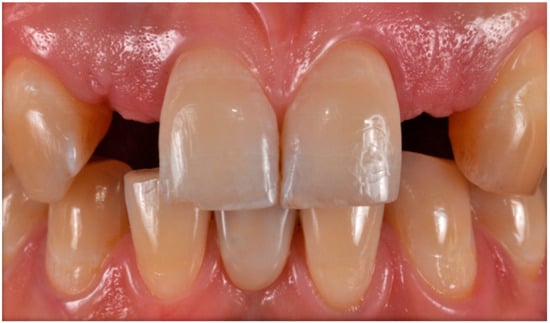

The case describes rehabilitating two congenitally missing lateral incisors in a young patient (38 years old) undergoing orthodontic treatment to create the necessary space for implant placement (Figure 1 and Figure 2). Two fibre-reinforced composite Maryland bridges (Tender Fiber Quattro—Micerium) were utilised for provisional rehabilitation (Figure 3, Figure 4 and Figure 5). Two Osstem TSIII 3.5 × 10.0 implants (1.5 mm subcrestal), two straight Osstem Zirconia abutments, and two-layered lithium disilicate crowns were employed for the definitive restoration (Figure 5, Figure 6, Figure 7, Figure 8, Figure 9, Figure 10, Figure 11, Figure 12, Figure 13, Figure 14, Figure 15, Figure 16, Figure 17, Figure 18, Figure 19 and Figure 20) [,]. The dental implant position was planned after a three-dimensional radiographic analysis in a prosthetically guided way. Patient rehabilitation was performed with an immediate post-surgery provisional (Maryland-type, cemented with a resinous cement) application. Subsequently, a delayed loading of the new provisional dental implant was retained (cemented with zinc oxide eugenol cement) and finally, definitive crowns (cemented with a definitive resinous cement) on Osstem® abutments were installed (3 months).

Figure 16. Gingival profiles (a,b) and inserted abutments (c,d).

Figure 17. Mucosal profile (a) and crown placement (b,c) (fabricated with lithium disilicate ceramics (e-max)).

Figure 20. Aesthetic integration: frontal (a) and lateral (b) views.